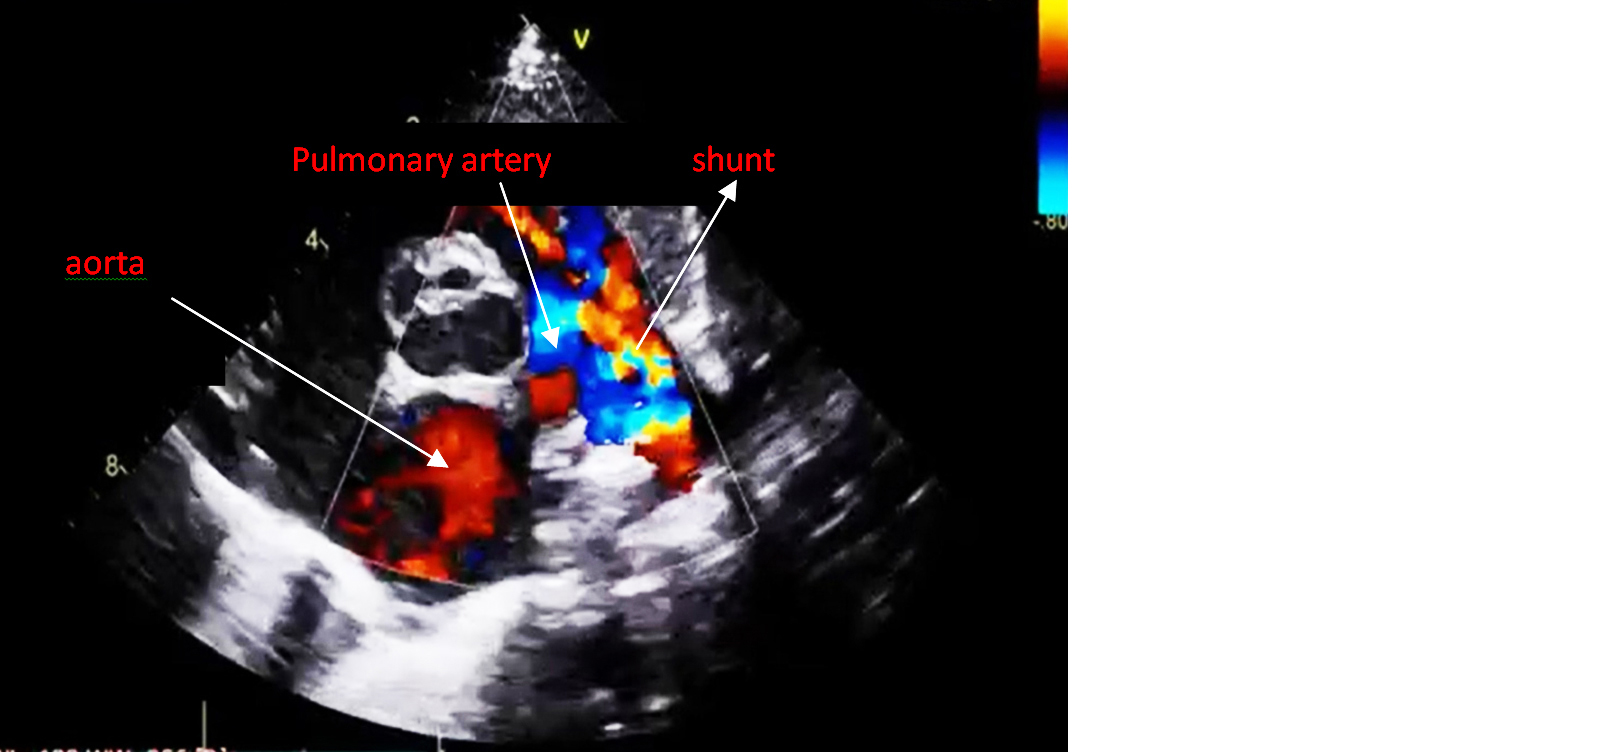

An echocardiogram revealed a patent ductus arteriosus with a residual shunt across the device. Normal left aortic arch, good biventricular function, no pericardial effusion (Figures 1 and 2). RT PCR was negative for COVID-19. Hematological investigations were within the normal range.

Figure 2: Echocardiogram of PDA with minimal residual shunt across the PDA device.